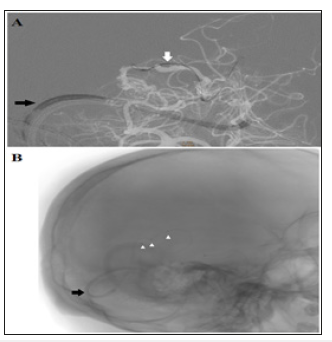

Figure 3:(A) Lateral (B) Oblique views of a super selective venography delineating the targeted nidal compartment of the AVM. (C&D) Lateral and oblique non-subtracted images “the same as in A&B” after final Onyx injection. The targeted compartment was totally occluded, with extension of Onyx toward small part of another compartment

Injection of Onyx® 18 was started by making a plug to occlude the vein to allow progress of Onyx into the nidus. The Onyx partially diffused also toward the other compartment. Finally, a sufficient occlusion of the nidus is reached. The other draining vein is left to act as a safety valve and drains the remaining part of the nidus (Figure 3).